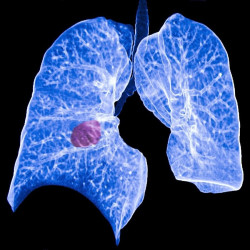

Las células expuestas a los carcinógenos ofrecen pistas para combatir los cánceres resistentes al tratamiento

Investigadores del Hospital General de Massachusetts (MGH), en Estados Unidos, han descubierto un mecanismo biológico que transforma las células expuestas a carcinógenos procedentes de factores ambientales como el tabaquismo y la luz ultravioleta en células inmunogénicas que pueden aprovecharse terapéuticamente para combatir los cánceres resistentes al tratamiento.